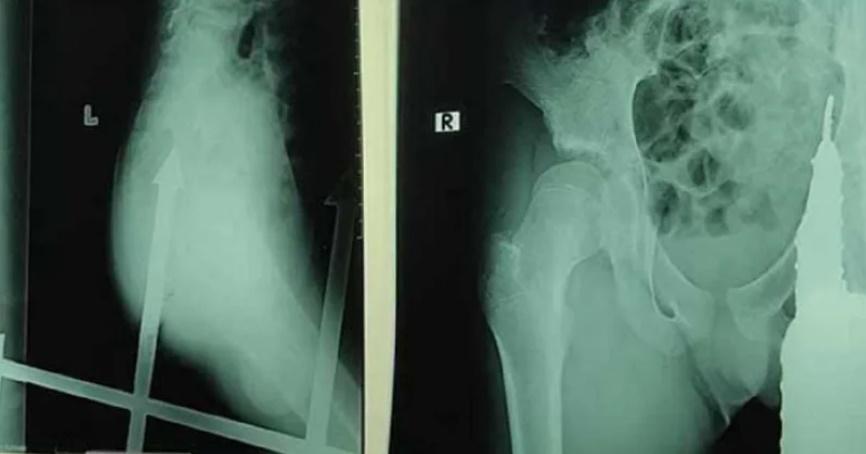

男童在醫院隨即照X光,醫生指,鐵刺插入男童臀部後,距離肛門只有少少距離,因此立刻進行手術,將鐵支移取。目前男童無生命危險,但未提及是否傷及其他器官。